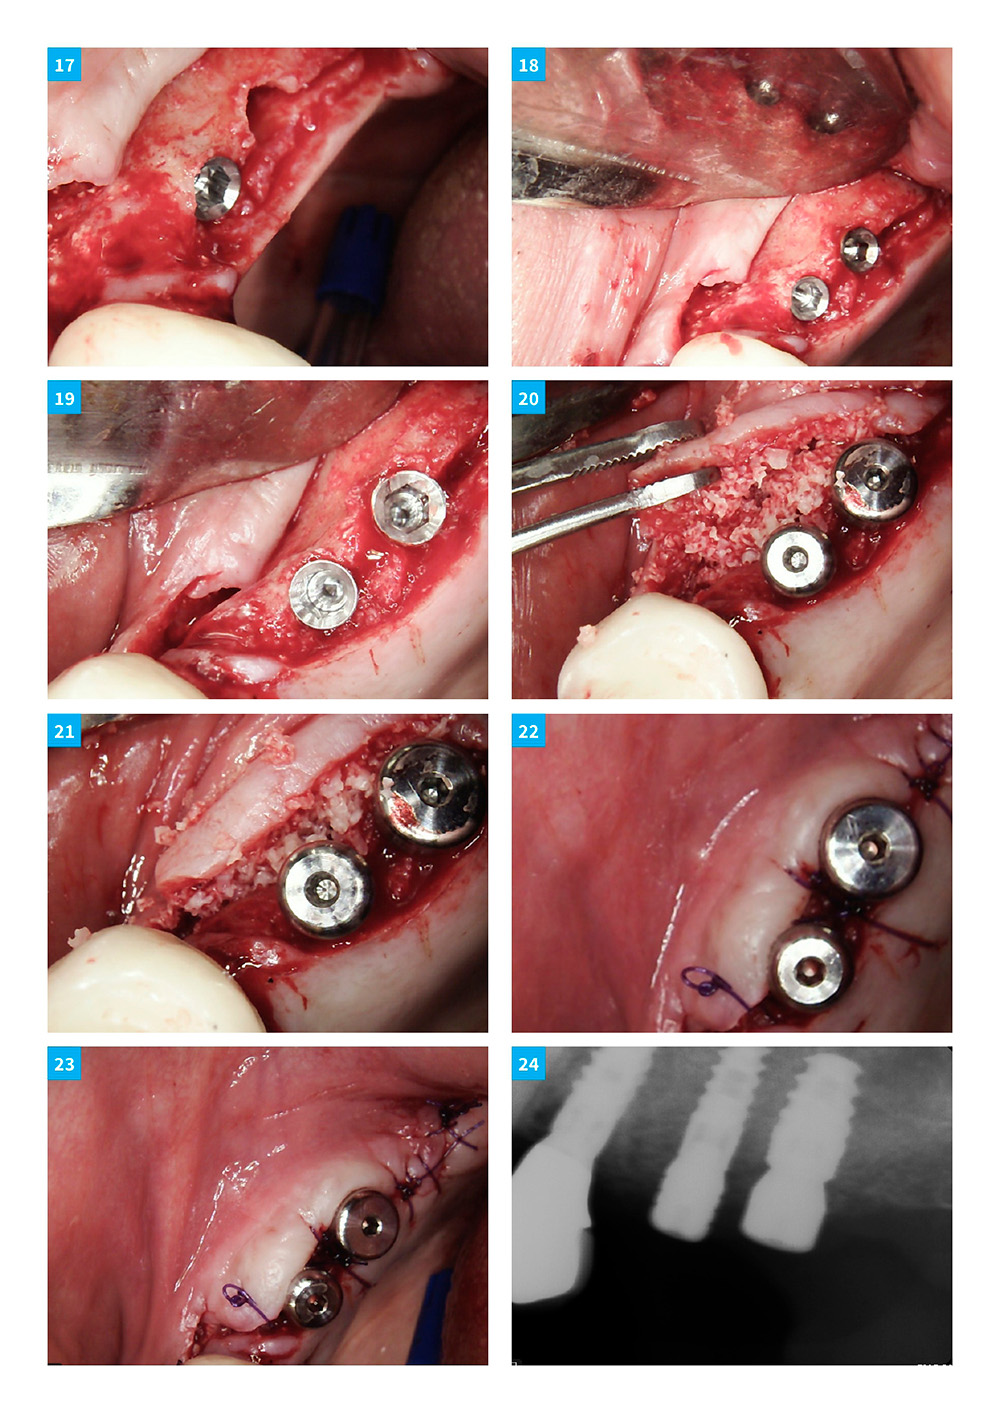

Dental Implant Continuum with DSI implants and products. Case 10

A year-long hands-on surgical program in Orange County & Silicon Valley, California. DSI Implants & products used exclusively.